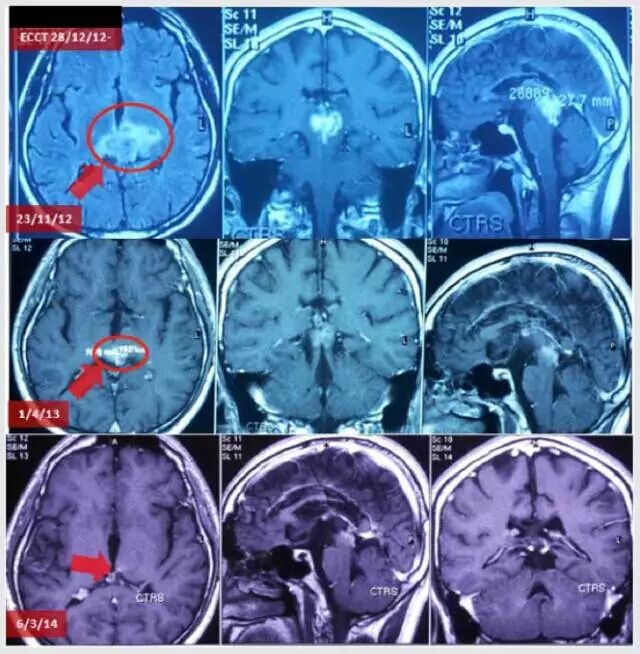

一、电场疗法

患者男性,22岁,诊断为松果体瘤,侵犯丘脑:肿瘤位于中脑(松果体区域)压迫丘脑(MRI 2012年11月23日),导致患者视力受损和严重头痛。ECCT治疗4月后,肿瘤体积逐渐缩小(MRI 2013年1月4日),患者症状持续改善。治疗15月后,MRI示肿瘤几乎消失(2014年3月6日),患者状况几乎回复正常。在这个病例里,肿瘤通过脑脊液流出道与第四脑室相连,因此死亡细胞可完全清除。单纯使用ECCT而不用手术有望完全消除整个肿瘤。